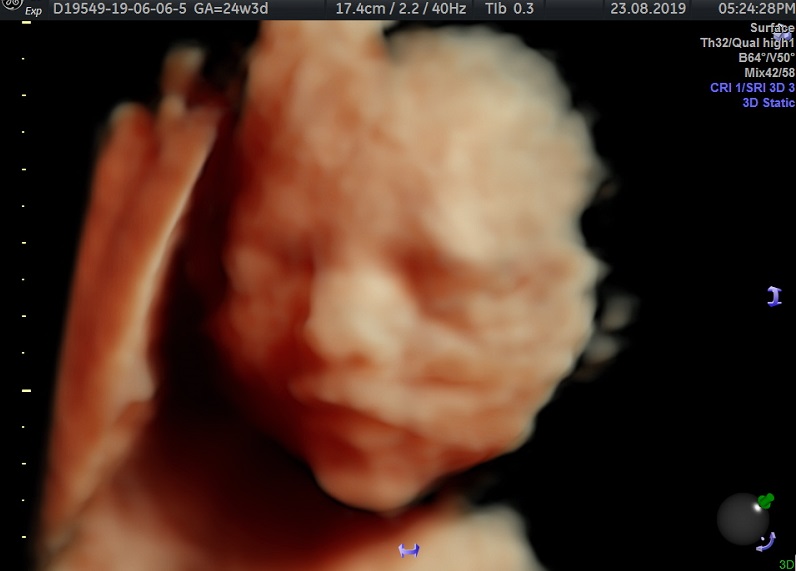

Modalidad de imagen ecográfica que permite evaluar, medir y capturar estructuras fetales superficiales e internas en 3 dimensiones (3D) y también en movimiento y en tiempo real (4D) con programas de realismo aumentado (HD LIVE) e imágenes tomografías fetales (TUI) mejorando significativamente la precisión en las mediciones fetales y la documentaciones de estructuras anatómicas.

Esta tecnología se puede utilizar desde la 6ta a la 40ma semana de embarazo.